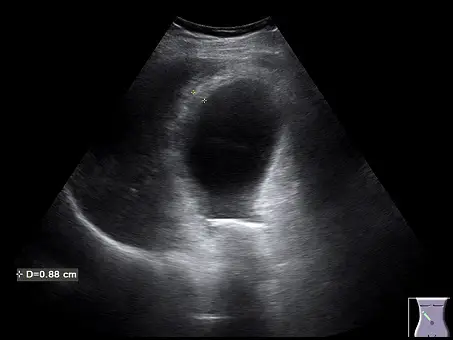

觀察提供的右上腹超音波影像:

- 膽囊壁增厚(Gallbladder wall thickening):影像左下角標示了膽囊壁的厚度測量值為

D = 0.88 cm(即 8.8 mm),明顯超過正常膽囊壁厚度的上限(通常為 3 mm)。 - 結石與後側音影(Gallstone with posterior acoustic shadowing):在膽囊頸部(neck)區域可見一明顯的高回音(hyperechoic)結構,其後方伴隨典型的無回音黑色帶狀陰影,即後側音影(acoustic shadowing),這是膽結石的標準特徵。

- 膽囊腫大(Gallbladder distension):呈現充滿液體的囊狀擴張構造,對應題目所述橫徑超過 4 公分。

根據《東京指引》(Tokyo Guidelines)及典型超音波診斷標準,診斷急性結石性膽囊炎的核心要素包括:確認膽結石的存在、膽囊壁發炎水腫(>3 mm)、膽囊腫大(橫徑>4 cm,長徑>8 cm),以及探頭壓迫時誘發的局部劇烈疼痛(positive sonographic Murphy's sign)。題幹的文字敘述與超音波測量圖(壁厚達 0.88 cm 以及結石產生的後側音影)完美契合這些診斷要件,因此最可能的診斷為急性結石性膽囊炎(acute calculous cholecystitis)。正確解答為 (A)。